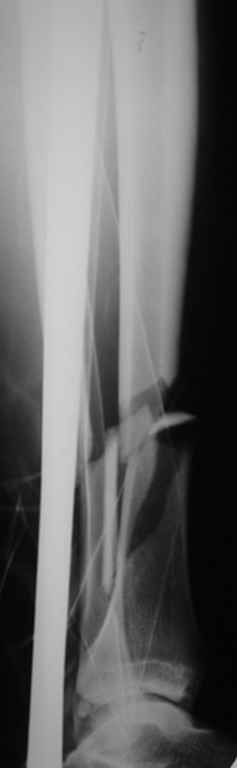

ЮАБ> Хотел-бы услышать Ваше мнение по поводу того, кто как относится к

ЮАБ> наличию свободных осколков в линии перелома и чем при этом

ЮАБ> руководствуется - размер, локализация, возраст и т.д.

Практически единственное, что делает необходимым разрез для манипуляций с промежуточным отломком бедренной кости - это его "застегивание" в илиотибиальном тракте по типу пуговицы в петле.

Когда при движениях в колене этот отломок на сантиметры смещается, создавая очевидный дискомфорт. Даже в этом случае репозиция отломка

именно в его ложе избыточна, достаточно осциллирующей пилой отсечь то, что выстоит над фасцией.

Отломок, расположенный так, как на показанных рентгенограммах бедра, обычно на снимках в 1-2 мес. уже располагается ближе к диафизу и

включается в мозоль.

На голени что-то сделать с отломком вынуждает угроза перфорация кожи, перекрытие отломком входа в канал. Не всегда надо делать разрез, можно и шилом чрескожно фрагмент сдвинуть. Наверно, еще и повреждение сосудистого пучка, когда "виновник" прямо поперек перерезанной артерии и лежит - такое не каждый за всю свою профессиональную жизнь

встретит.

То есть в представленных ситуациях при штифтовании ни на бедре, ни на голени не нужно делать ни открытую, ни закрытую (с помощью шильев,

спиц, еще каких-то "джойстиков") репозицию. Все, что нужно - восстановить ось, длину и ротацию.

Перелом большеберцовой кости почти околосуставный, могут потребоваться дополнительные меры для восстановления оси (отклоняющие спицы или винты), и запирающих винтов в дистальный отломок желательно побольше. Задний край не сломан ли там, не разобрал по этим снимкам.